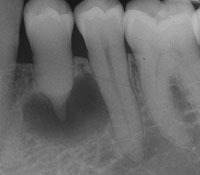

Caries Radicular

La caries radicular es la descomposición del cemento y la dentina en la raíz del diente, común en personas mayores con recesión gingival.

Los pacientes pueden experimentar sensibilidad y dolor en la raíz expuesta.

El tratamiento incluye la eliminación de la caries y la restauración de la raíz. La prevención incluye una buena higiene oral y el uso de flúor.